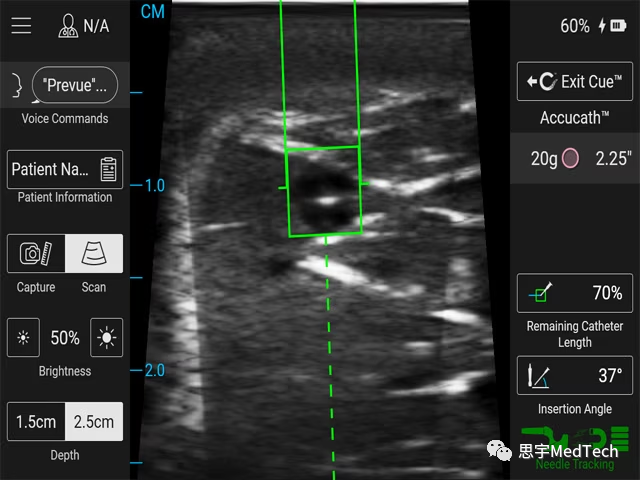

BD Prevue™ II外周血管通路系统(Prevue™ II peripheral vascular access system)是BD推出的新的超声设备,通过实时针头深度标记来辅助静脉插管。

除了特殊的探针之外,BD Prevue™ II系统还配备了BD Cue™针头追踪系统,可以为针头的轨迹提供高质量的超声图像。模拟研究显示,将针头追踪系统与超声引导相结合,有助于减少静脉插管的次数和成功进入血管的时间。美国超声医学协会称,这可能使血管通路操作对临床医生和患者更加安全和便利。

Prevue™ II系统可以通过集成的BD Cue™针头追踪系统,让医生可以在屏幕上通过虚拟的针头运动轨迹将针头与血管对齐。据称,使用针头追踪系统与超声结合比只使用超声更容易插管。